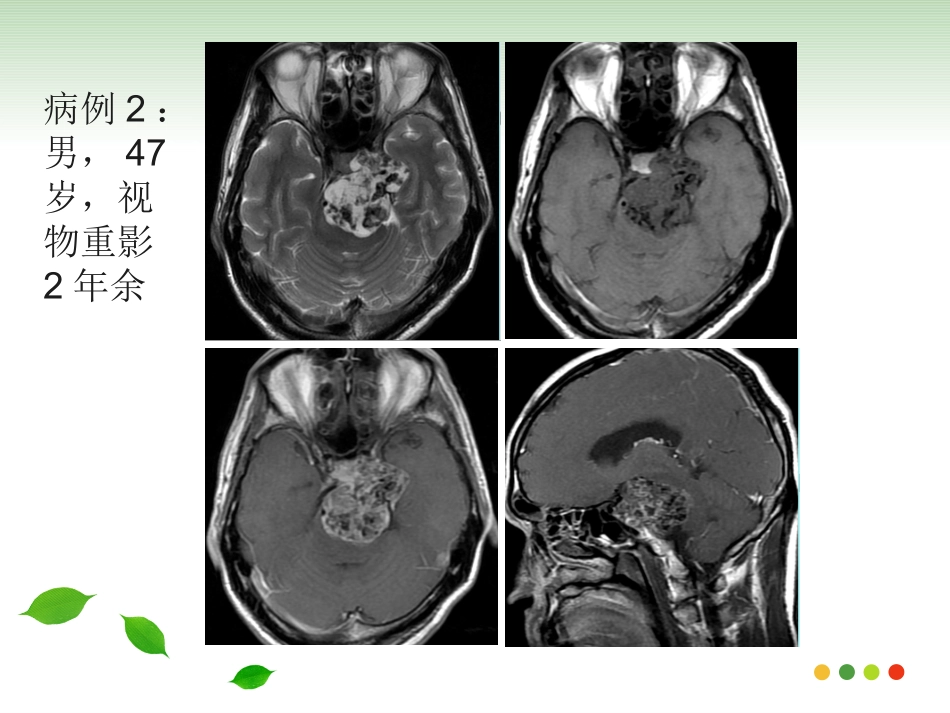

病例1:女,10岁,视物重影1月余病例2:男,47岁,视物重影2年余病例一病例二斜坡脊索瘤的影像诊断斜坡脊索瘤的影像诊断福建医科大学附属第一医院影像科2017级周晓芳发病机理发病机理•脊索是人体脊柱的原基,形成于胚胎期的第3周,上方由头盖骨的Rathke’s袋限制在蝶骨,向下和咽部相连,接着穿过齿状突和椎体中央•胚胎发育成为颅底的一部分和脊柱,残存的脊索组织可发展成为脊索瘤。概述概述•脊索瘤是一种比较少见的来源于脊索胚胎残余物的低度恶性肿瘤。•占颅内肿瘤的1%,占所有原发性骨肿瘤的4%•斜坡由枕骨基底部和蝶骨体共同组成,上界为鞍背,下界为枕骨大孔前缘,分上、中或下区。上区相当于蝶骨体,中区为蝶枕软骨结合处,下区为枕骨基底部,以中区最多见临床表现临床表现•可发生于任何年龄,成年人多见,30-40为高峰•男女比例2:1•生长缓慢,症状隐匿•最常见复视、颅神经麻痹及头痛;外展神经受累最常见,头痛通常在枕部或眶后位置病理表现病理表现•光镜下脊索瘤细胞胞浆丰富、内含黏液和大量空泡,也称液滴细胞;瘤细胞呈索条样分布,其间可见大量的黏液基质。•分为两个亚型:以液滴细胞为主、缺少软骨成分者为经典型;局灶性的软骨组织点缀在肿瘤基质内即为软骨瘤样型,软骨成分含量不一。治疗及预后治疗及预后•手术切除,辅以放射治疗•远处转移罕见,7%-14%可发生肺,肝,骨或淋巴结转移•5年生存率为60%〜70%•软骨瘤型预后更好,且软骨含量越高,预后越好。局部复发远处转移影像表现-CT影像表现-CT•大小不一,多在2-5cm之间•位于中心,广泛溶骨破坏•钙化不规则,通常被认为代表骨质破坏而不是肿瘤本身的营养不良钙化。•中度至显著强化,可见无强化粘液区影像表现-MRI影像表现-MRI•T1WI呈低信号,T2WI为明显高信号,软骨瘤型T2WI信号较低•常信号不均,可为陈旧出血、钙化、高蛋白粘液、纤维间隔或死骨•中至显著“蜂窝状”样、渐进性强化•邻近血管受压推移或部分包绕,但很少狭窄肿瘤扩散肿瘤扩散女,66岁,右眼视物模糊4年,右眼睑下垂半年女,66岁,右眼视物模糊4年,右眼睑下垂半年女,59岁,双眼视物模糊10余天女,59岁,双眼视物模糊10余天男,14岁,头痛伴反应迟钝、记忆力下降3个月男,14岁,头痛伴反应迟钝、记忆力下降3个月鉴别诊断鉴别诊断•软骨肉瘤•鼻咽癌•侵袭性垂体瘤•脑膜瘤•转移瘤软骨肉瘤软骨肉瘤•间叶源性肿瘤•偏中心性生长,中心多位于岩枕裂,或鞍旁•信号与脊索瘤相似,强化常轻微,可为结节状、分隔状及弥漫样•ADC值较高•钙化呈点、环、弧形男,47岁,视物双影2年余男,47岁,视物双影2年余鼻咽癌鼻咽癌•中心以鼻咽部为主,一侧或双侧咽隐窝的变浅消失,局部可见偏侧软组织肿块形成•T1WI呈等信号,T2WI信号稍高,强化明显•骨质破坏偏向一侧,肿瘤内缺乏钙化•颈部淋巴结肿大•临床鼻咽部的组织活检可明确诊断女,75岁,发现左颈部肿物1月余女,75岁,发现左颈部肿物1月余侵袭性垂体瘤侵袭性垂体瘤•T1WI为等信号,T2WI为等-高信号,常出血、坏死及囊变液液平多见•向鞍上生长明显时,可见束腰征,CT显示蝶鞍扩大,鞍底下陷,骨质破坏吸收•增强扫描明显强化,正常垂体不存在•易出现内分泌疾病的症状女,47岁,视物模糊1月余女,47岁,视物模糊1月余脑膜瘤脑膜瘤•CT均匀等密度,MR信号与脑实质相近•多以宽基底与颅骨相邻,明显均匀强化,硬脑膜尾征•骨质增生硬化,而骨质破坏少见男,47岁,左眼视物不清半年转移瘤转移瘤•原发病史,常为多发•T2WI呈等或低信号,肿瘤内缺乏钙化•骨质破坏较软组织肿块范围大女,46岁,肺癌病史小结小结•30-40为高峰,最常见复视、颅神经麻痹及头痛•肿瘤多在2-5cm之间•边界清楚,不规则型及分叶状多见•溶骨性破坏•T2WI为明显高信号•中度至显著强化,呈蜂窝样、颗粒样且持续强化•邻近血管受压推移或部分包绕,但很少狭窄